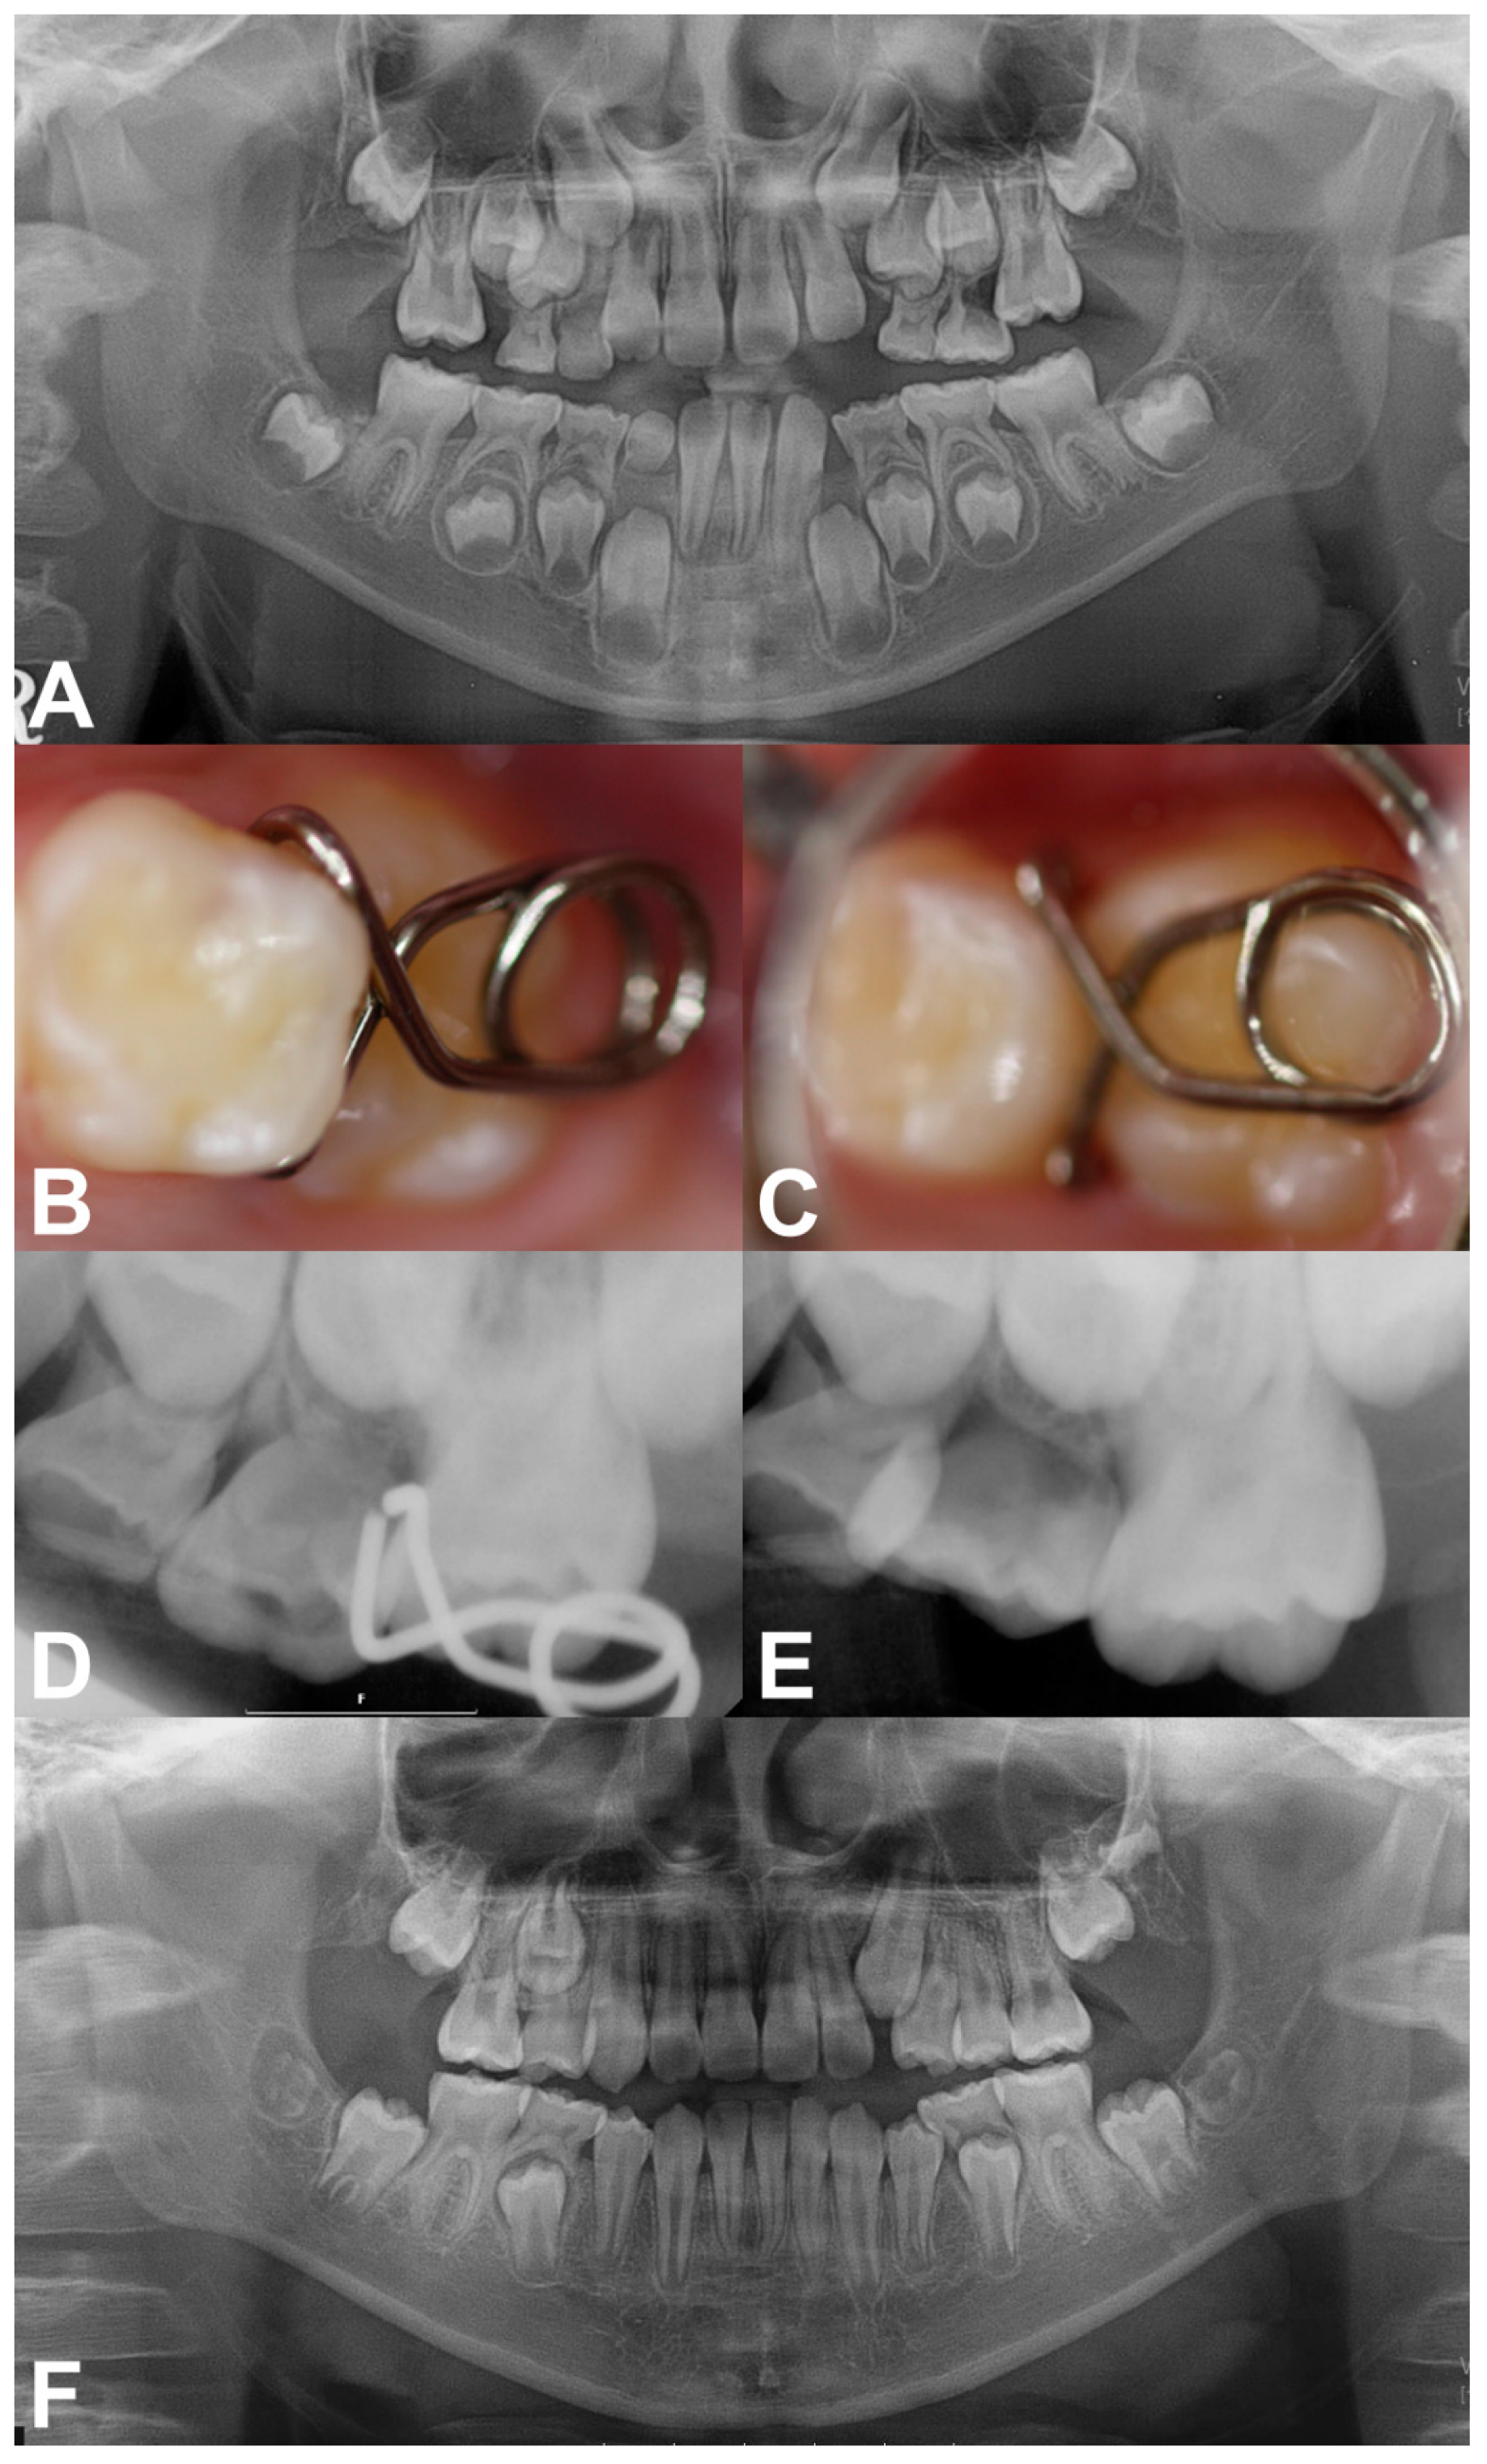

Case 2: A 7-year-old girl without any relevant medical history was referred from a local clinic for her mesially tilted right maxillary first molar locked under the adjacent primary second molar. Clinical and radiographic examination revealed an approximately 2.5 mm deep entrapment of the right maxillary first molar with considerable root resorption of the right maxillary primary second molar (Figure 3A). There were no other dental abnormalities. We inserted a mRS to align the first molar after infiltrative anesthesia. The horizontal spring was placed directly above the occlusal surface of the right maxillary first molar without premature contact. The two engaging vertical arms completely embraced the mesial surface of the first molar (Figure 3B,C). One month after the insertion, a distal movement of approximately 1 mm was observed on the periapical radiograph (Figure 3D). Within 3 months, the mesially tilted right maxillary first molar escaped the entrapment, moving to its normal position with no sign of increased mobility of the right primary second molar after removal of the mRS (Figure 3E).

Figure 3. Pre-treatment and treatment progress images of case 2. (A) Panoramic radiograph revealed the ectopic eruption of the right maxillary first molar. (B,C) Intraoral photograph and periapical radiograph after insertion of the mRS. (D) Periapical radiograph obtained at the 1-month checkup. (E) 3 months after treatment showing a corrected right maxillary first molar.